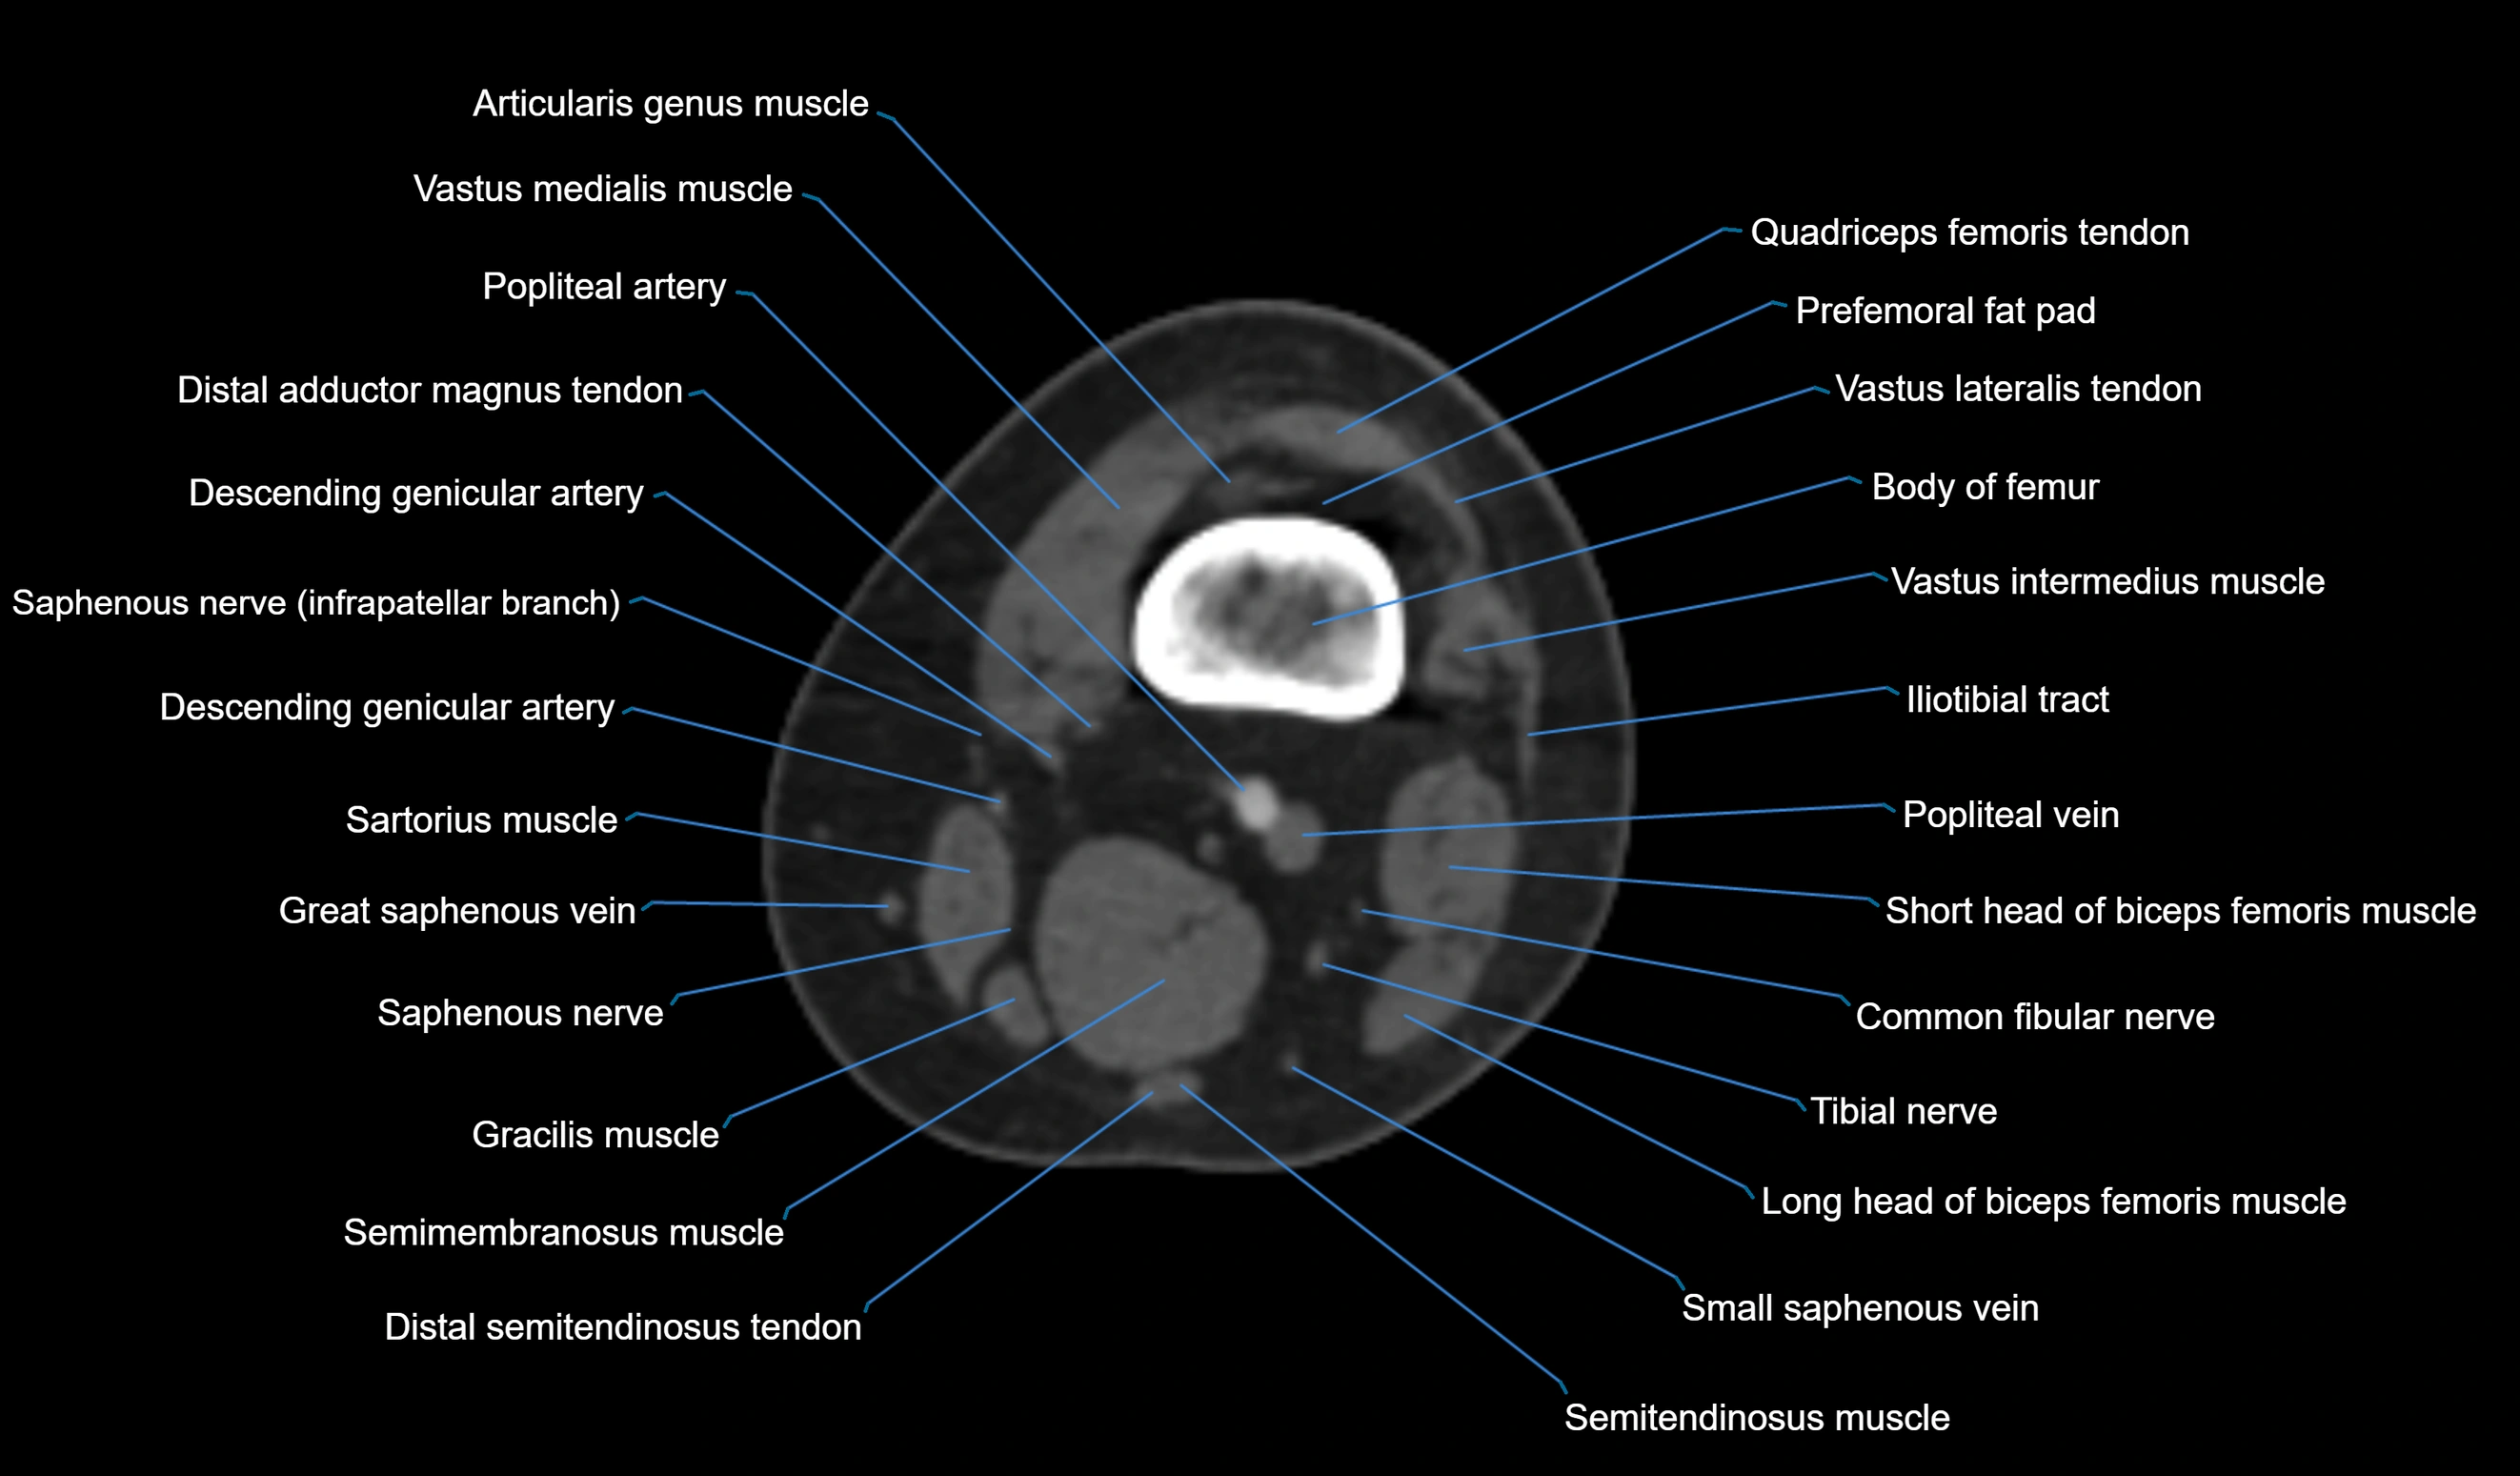

- Biceps femoris muscle (Long head)

- Biceps femoris muscle (Short head)

- Body of femur

- Descending genicular artery (Articular branches)

- Descending genicular artery (Saphenous branch)

- Distal adductor magnus tendon

- Distal quadriceps femoris tendon

- Distal semitendinosus tendon

- Distal vastus intermedius tendon

- Distal vastus lateralis tendon

- Distal vastus medialis tendon

- Popliteal artery

- Popliteal vein

- Prefemoral fat pad

- Saphenous nerve

- Sartorius muscle

- Semimembranosus muscle

- Semitendinosus muscle

- Small saphenous vein

- Tensor fasciae latae muscle

- Tibial nerve

- Vastus lateralis muscle

- Vastus medialis muscle

- great saphenous vein